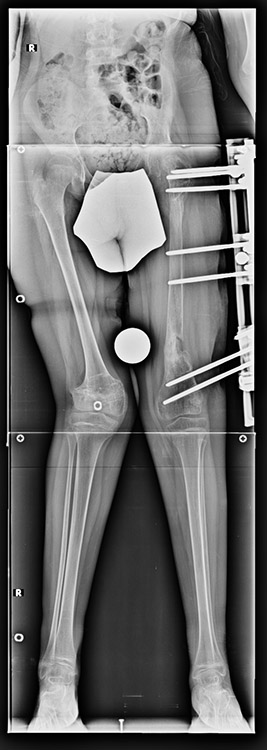

Many patients don’t want to use a shoe support thicker than 2 cm. For length differences between 2 cm and 5 cm, shortening may be considered for tall patients. This can be performed in growing children with a small, minimally invasive, uncomplicated procedure called epiphysiodesis. This means surgical disruption of one or more growth plates. There is a growth plate at the ends of femur, tibia and fibula; this procedure does not halt all growing of the leg. The growing of the longer leg is calculated and halted to allow the shorter leg to catch up.If the procedure is performed at a too early or too late age, the correction may be too much or too little, respectively. Hence, it is important to accurately calculate the most appropriate age for epiphysiodesis. When and at which bone segment epiphysiodesis will be performed shall be calculated by the doctor using different methods such as Gren-Anderson diagram, Moseley curve or Paley’s multiplier method.Epiphysiodesis is not an option for adults because growth plates ar closed. In adults, a bone segment has to be excised surgically in order to shorten the leg. This is usually performed at femur and bone is later fixed with an intramedullary nail. The biggest advantage of this system is that it acutely provides limb length equality for discrepancies less than 5 cm. The common disadvantage of epiphysiodesis and shortening is the shortening of total height of the patient. Because we don’t advice shortening more than 5 cm, height loss can’t be more than 5 cm. For patients who don’t want an epiphysiodesis or shortening operation for length inequalities less than 5 cm, limb lengthening can be preferred in order to equalize the length difference.This can be combined with epiphysiodesis and shortening to decrease a need for another lengthening operation or to decrease the lengthening amount required.